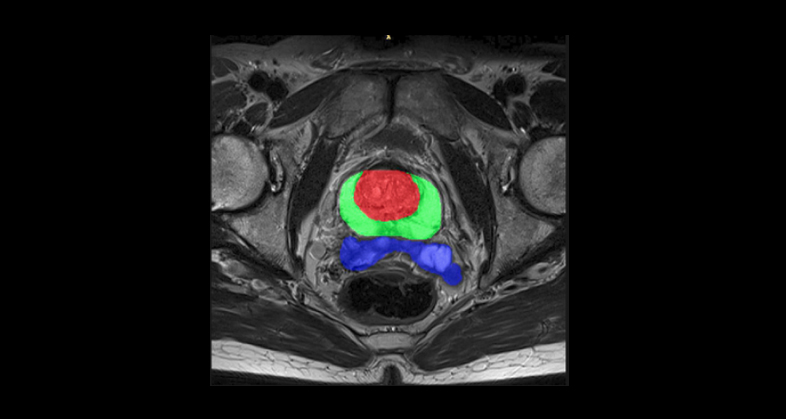

Our tissue-agnostic AI methods are applied at each stage of drug development programs. First we apply our AI techniques to harmonize image quality across hospitals and scanner models, then we perform automated organ and lesion detection. A tissue characterization follows to extract a signature based on the most relevant radiomics-based and deep features. These features are then used to develop predictive models of tumor growth, treatment response, overall survival, disease free survival, among many other patient outcomes.